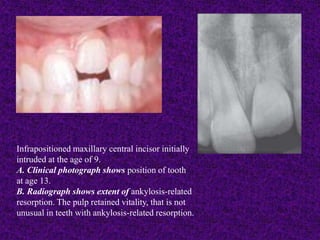

Infrapositioned maxillary central incisor initially

intruded at the age of 9.

A. Clinical photograph shows position of tooth

at age 13.

B. Radiograph shows extent of ankylosis-related

resorption. The pulp retained vitality, that is not

unusual in teeth with ankylosis-related resorption.